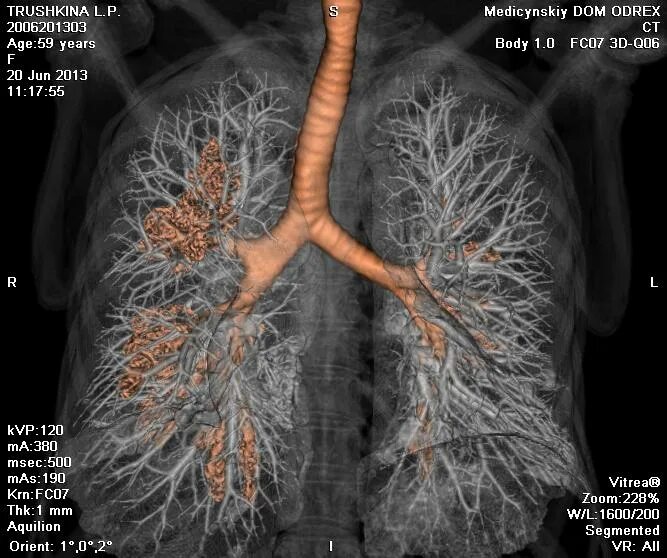

Что показывает мскт